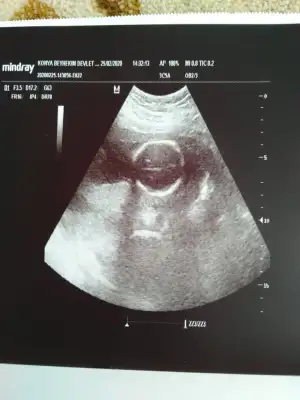

Arkadaşlar iyi aksamlar. Bugün ikili test yaptırdım doktor bişey söylemedi. 13 haftalık tam olarak. Cinsiyet tahmini yapabilir misiniz?

• 20200224_224652.webp

20200224_224652.webp

15,3 KB · Görüntüleme: 88